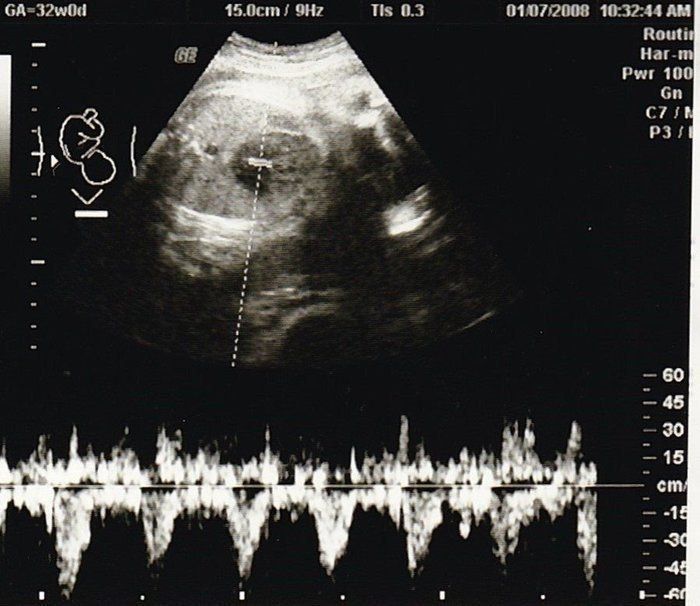

ママにエールさんの妊娠32週目のエコー写真

推定体重1803g。「平均的だから、成長も問題ない」と先生から説明を受けました。赤ちゃんは性別をまだまだ内緒にしているよう。出産も近づきつつあるこの時期、動けるときは運動を兼ねてお散歩したり、劇場などで開かれるランチタイムコンサートなどに行ったりしました。音楽と共に胎動を感じるときは、我が子と一心同体でその瞬間を楽しんでいるような幸せな心地がしました。